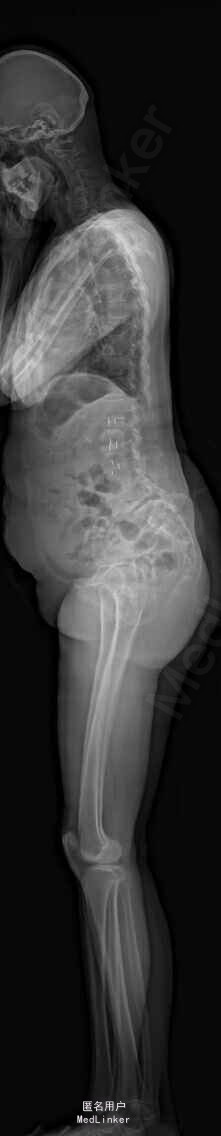

主诉:右下肢麻木伴驼背11年余 病史:患者女性,64岁,11年前无明显诱因出现右下肢疼痛,休息后好转。未予重视,后出现右下肢麻木感,逐渐小狐仙右臀部坚硬,驼背,伴跛行。常感双腿酸胀,腰部疼痛。自行步行距离小于200米,即会发生右下肢僵硬,麻木疼痛。X线检查示腰椎侧弯

查体:脊柱侧弯,上肢无麻木,疼痛感觉异常,腰部右侧疼痛,右下肢及右臀部疼痛,麻木感。双侧肌力及肌张力可,膝腱反射(+),踝反射(+),病理征(—),直腿抬高试验。右侧40度,左侧55度。 辅助检查:腰椎x线片:腰椎侧弯,腰椎退行性改变,L5椎体略行前滑脱 脊柱全长:胸腰段呈S形,L5椎体向前滑脱,L3椎体略变扁,颈胸腰椎退行性改变 MRI:脊柱侧弯,L2-3,L3-L4,L4-L5,L5-S1椎间盘突出,相应节段椎管狭窄

诊断:腰椎侧弯,腰椎椎管狭窄 治疗:手术矫形:早期侧路减压融合,后期再行后路固定。